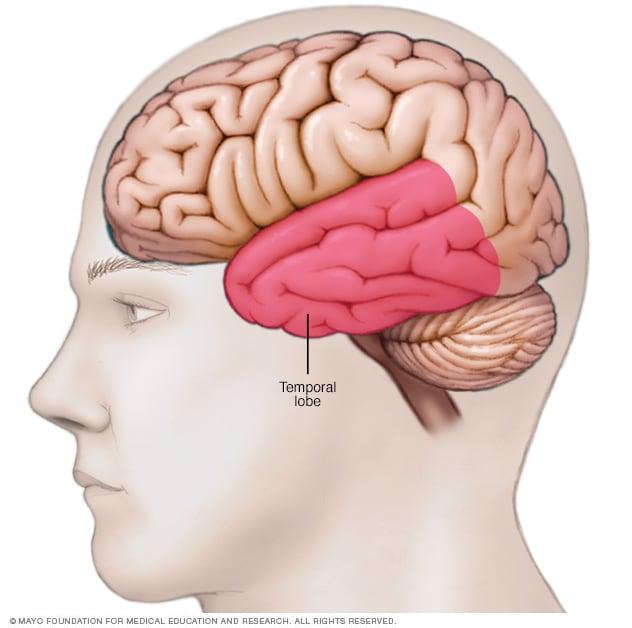

Location of temporal lobe

The temporal lobe is located along each side of the brain.